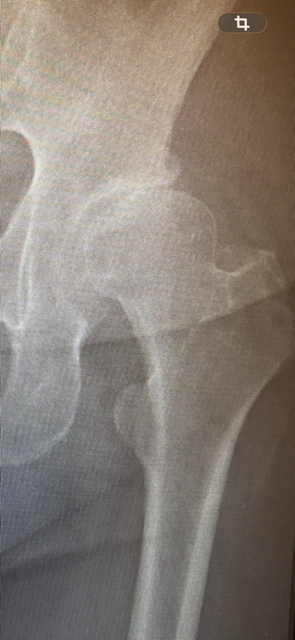

2026/03/23軟骨再生治療(股関節) 変形が進み、軟骨が消滅していましたが、関節が正しい位置に少しずつもどり、酸素や栄養が届き、結果軟骨が再生しました。 【BEFORE】 【AFTER】 カテゴリー 股関節 症状別改善事例 股関節:変形性股関節症 股関節:骨盤調整